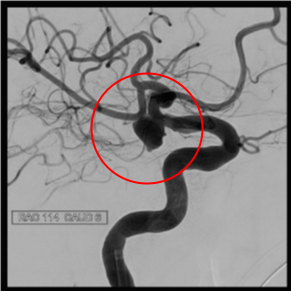

前交通動脈瘤

術前の造影写真です。〇内に脳動脈瘤が造影されています。

動脈瘤内にマイクロカテーテルを挿入しステントを展開しています。

術後の造影写真です。主幹動脈は温存できており、動脈瘤は造影されなくなっています。